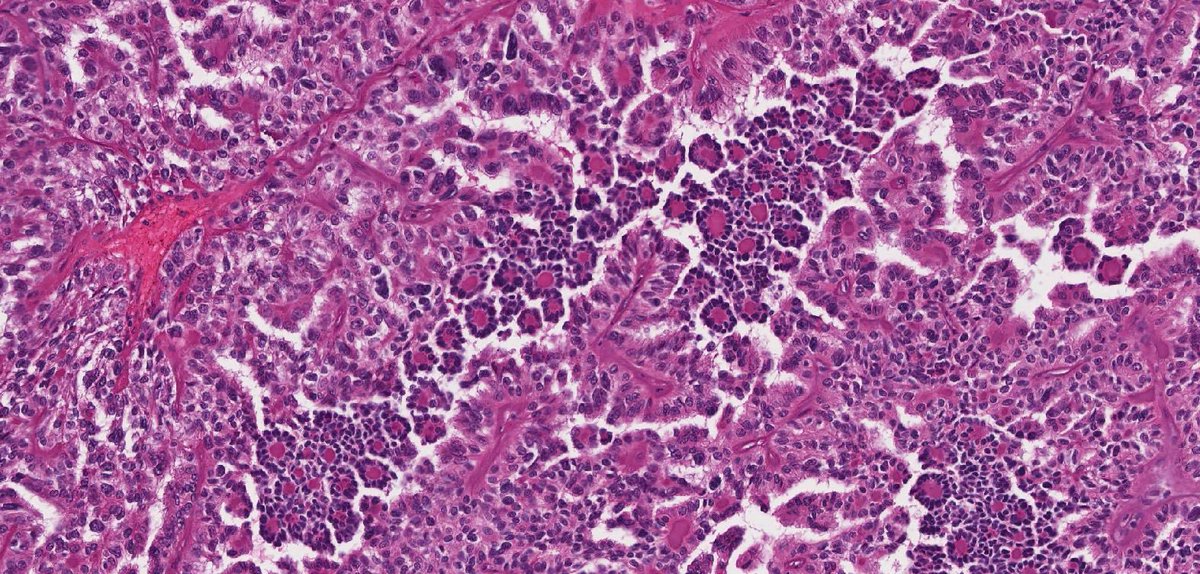

#slidearchiveseries biphasic hyalinizing psammomatous renal cell carcinoma

#gupath #pathtwitter #pathoutpic

🔬 biphasic pattern: smaller cells around basement membrane material within larger acini, forming a glomeruloid pattern

🧬 assoc with somatic mutations in NF2 gene